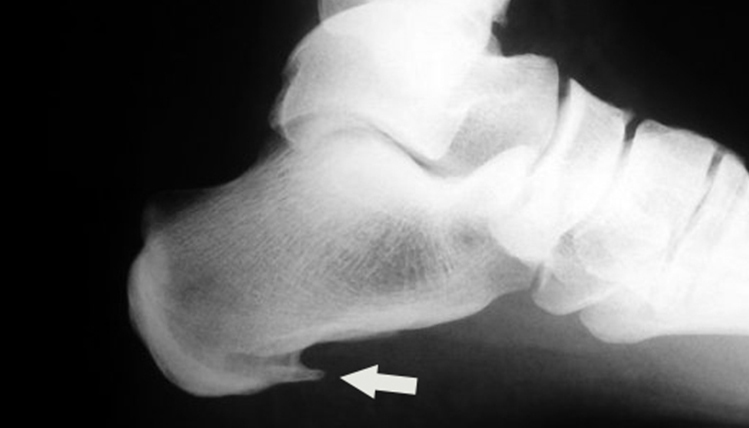

Diferencia entre fascitis plantar y el espolón calcáneo

En ocasiones se confunde la fascitis plantar con el espolón calcáneo. Podemos hablar de espolón cuando observamos una calcificación del tubérculo postero-medial del calcáneo en las pruebas radiológicas.

En esta radiografía se observa un “saliente puntiagudo” desde el talón hacia el interior del pie, indicando la patología de espolón calcáneo. Si en las pruebas no aparece dicha calcificación, se trata entonces de fascitis plantar.

Los síntomas y el tratamiento van a ser muy parecidos en ambos casos. El espolón aparece por mantener una tracción continuada de la fascia contra el calcáneo. Esa tensión aparece en la fase inicial la fascitis plantar, y si se mantiene en el tiempo, posiblemente generará el espolón calcáneo. El objetivo del tratamiento es “destensar” la fascia para que disminuya la inflamación y el dolor.

Se puede afirmar, aunque con algunos matices, que el espolón calcáneo es la continuación natural de una fascitis plantar mantenida en el tiempo.